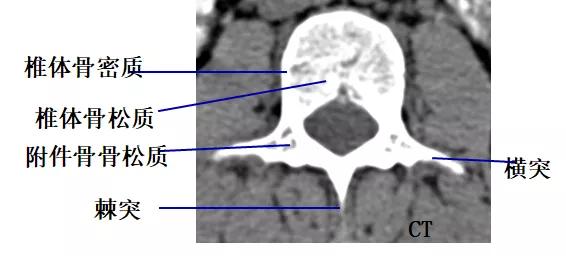

CT片所见骨质结构

椎体、椎板、椎弓根、关节突、横突、棘突。

CT断层表现

1.脊椎及附件骨

骨皮质: 位于椎体及附件的边缘部,CT表现为致密、连续的线状或带状影。

骨松质:位于骨结构的中央部,CT表现为细密的网格状影,边缘清楚。